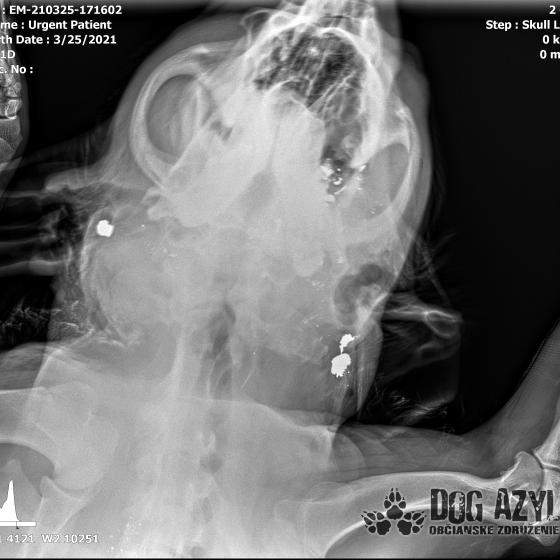

Strela zasiahla Barisa v oblasti lícnej kosti, ktorá mu rozdrvila sánku a následne putovala cez krk až po krčnú chrbticu. Úlomky z guľky (neviem ako sa to odborne volá) sa roztrieštili na "milión" kusov počas svojej cesty. Tieto úlomky sú všade (ako vidieť aj na RTG). Jeden (alebo niekoľko týchto úlomkov) sa dostali až po miechu, ale našťastie ju neprerazili. Toto spôsobilo, že Baris citlivosť v nohách na ľavej strane sice má, ale má poškodenú motoriku. Tieto úlomky sa z oblasti stavcov, miechy aj krku dnes odstránili, ale Barisko z ďaleka nemá vyhraté. Miecha je totiž zakrvácaná (opäť sa ospravedlňujem za nepresnosť a laickosť) a to, že ako veľmi je poškodená, alebo či jeho slabosť bola spôsobená "iba opuchom" sa ukáže cca do 24 hodín. Ak Baris nedajbože do zajtra stratí citlivosť v nohách, tak.. žiaľ... Ale! ak citlivosť zostane, prípadne nastane aj zlepšenie, tak vzplanie plamienok ďalšej nádeje a bojujeme ďalej!